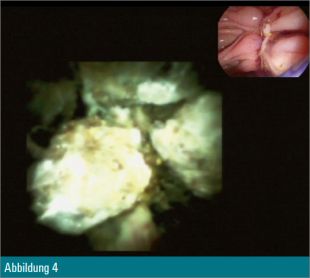

Eine 55-jährige Patientin wurde wegen eines Tonnenkonkrements im Ductus choledochus zur ERCP vorstellig (Abbildung 1). Nach Papillotomie erfolgte zusätzlich eine Ballondilatation der Papille auf 12 mm. Anschließend wurde mit dem Cholangioskop in den Ductus choledochus eingegangen (Abbildung 2) und eine elektrohydraulische Zertrümmerung des Konkrements unternommen (Abbildung 3).

Trotz Fragmentierung des Konkrements (Abbildung 4) waren mehrfache mechanische Lithotripsien mit dem Dormiakörbchen in derselben Sitzung notwendig. Schlussendlich konnten alle Fragmente erfolgreich mit dem Ballon geborgen werden (Abbildung 5).